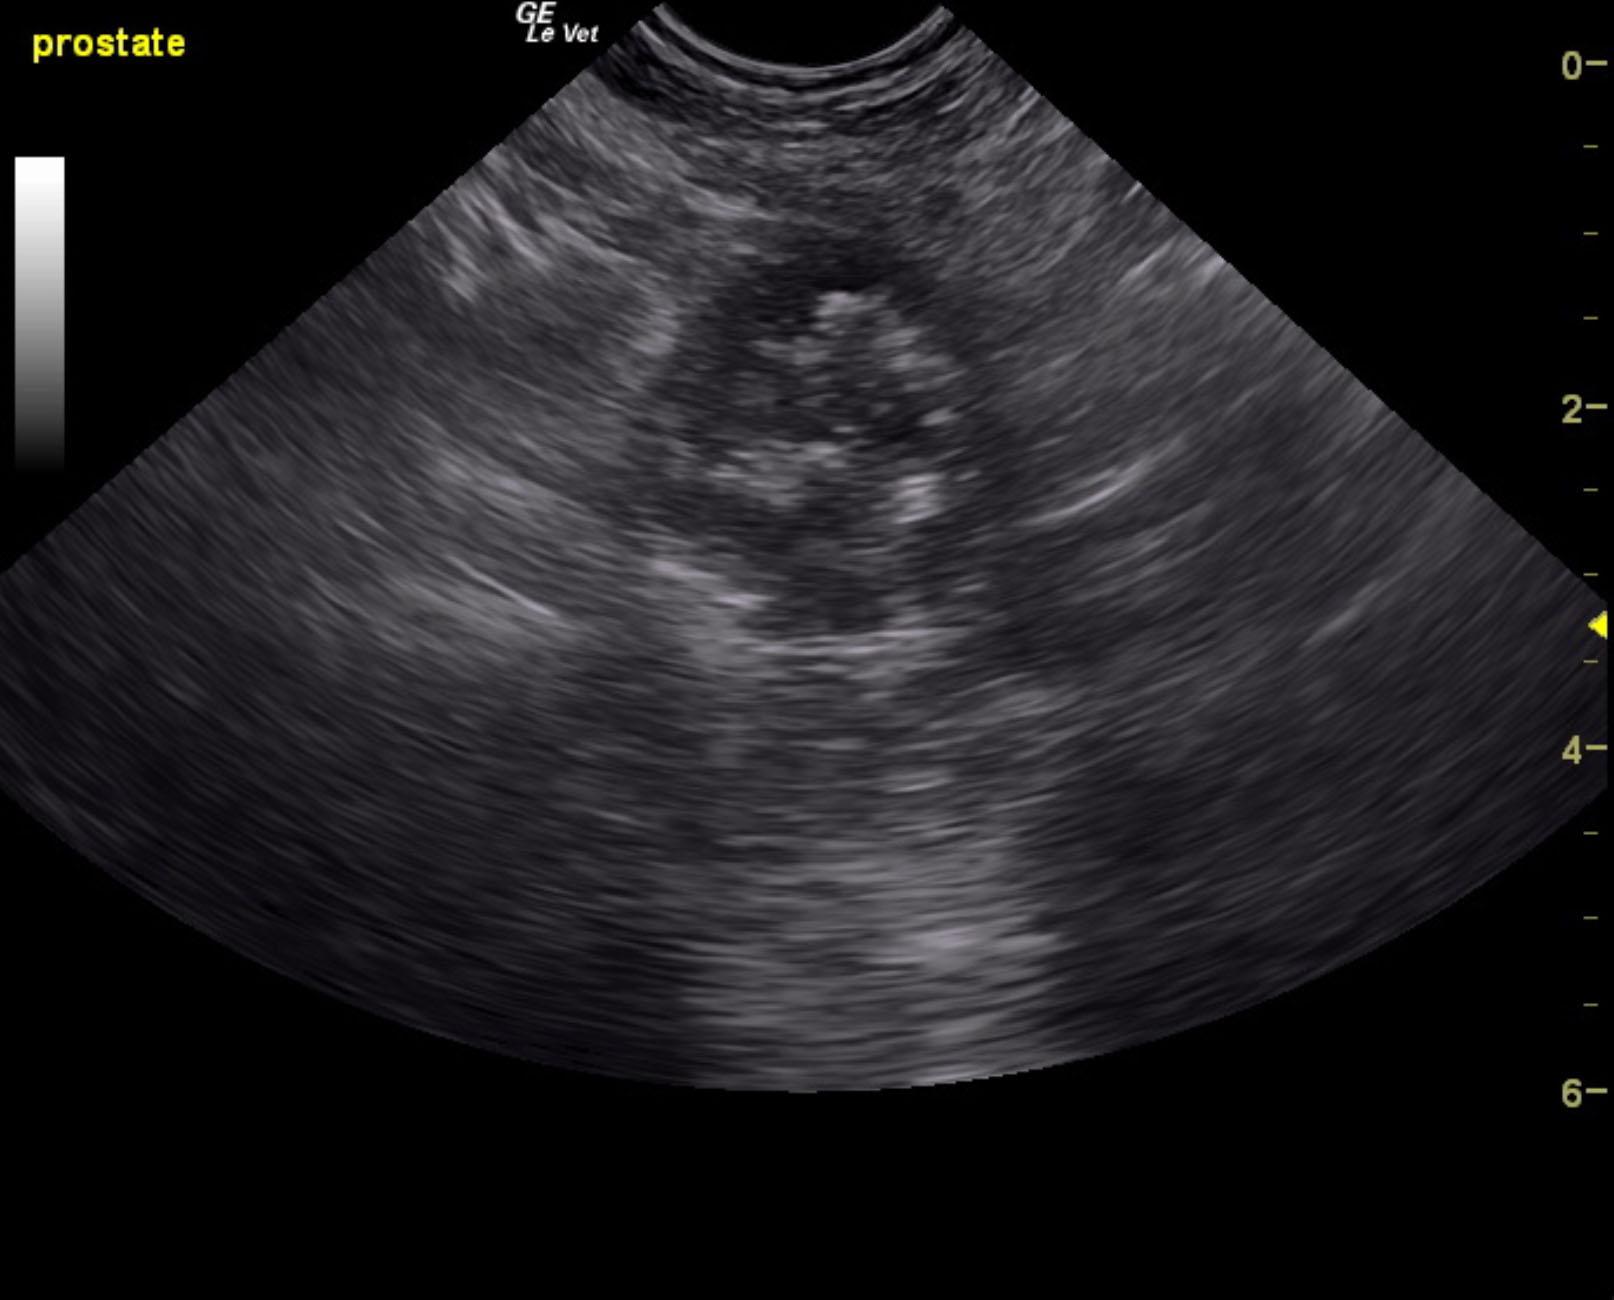

The prostate in this patient was enlarged with multi focal areas of mineralization. This is strongly suggestive for prostatic carcinoma. Ultrasound-guided FNA is recommended to confirm. Significant power Doppler vascularity was noted to the prostate. The prostate measured 3.76 x 2.1 cm with cauliflower projection into the cystourethral junction and invasion into the post prostatic urethra. Deviation of the descending colon was noted. This is owing to the prostatic pathology, which is responsible for the clinical signs.